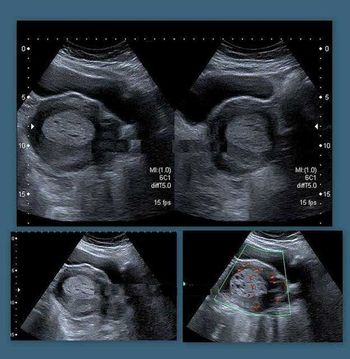

What is your diagnosis based on these images of the fetal heart?